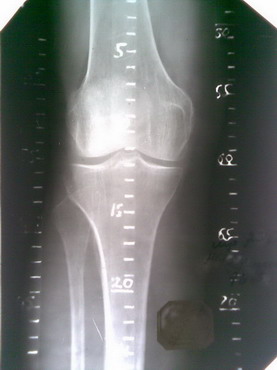

Сделаны метки цапон-лаком |  После травления в FeCl3 |  После пропайки оловом |  Окончательный вид |  Рентгенограмма | Помог опыт юного радиолюбителя. Для изготовления необходимо приобрести текстолит (фольгированный односторонний) с нанесенным слоем меди с одной стороны (для т.н. печатных (монтажных) плат - продается в магазинах радиодеталей, да и все остальное купил там же, обошлось в сумму рублей 70). Выпиливается полоса по необходимой ширине и длине. В данном примере шириной 1,5 см, длина 25 см (длиннее заготовки не нашлось, 3 шт). Затем цапон-лаком по меди (предварительно пройтись шкуркой, а то краска потом может отвалиться) наноситься гусиным пером (иглой или другим подручным средством) необходимый рисунок (метки, цифры - аккуратнее всего получилось бы у художника). Иногда лак растекается, страшного ничего нет, когда высохнет - можно поправить (счистить), например скальпелем. Говорят, что рисунок можно нанести и фломастером, но не каждым, искать методом тыка (захватив с собой в магазин плату, нанести по одному штриху разными фломастерами, естественно запомнить какой где, и травить. Где приемлемый результат, тот и купить). Но лично я не проверял.После высыхания лака (несколько минут), заготовка опускается в раствор хлорида железа (хлористое железо, хлорное железо, FeCl3) для травления монтажных плат. Концентрация раствора по большому счету не имеет значения, но лучше хлорида железа не жалеть, травится быстрее (а еще лучше помешивать теплый раствор), уходит примерно минут 20-40. Т.о. закрашенные места остаются, а неокрашенные растворяются. Далее лак стираем ацетоном (у меня оказалась жидкость для снятия маникюрного лака с витаминами) и еще раз шкурим очень мелкой наждачной бумагой. Затем берем паяльник, канифоль, припой и наносим на медные метки припой. Совет: чем мельче рисунок, тем сложнее его пропаять - припой сливается, в этом случае нужно воспользоваться зубочисткой и пока олово расплавлено, попытаться его убрать. Кроме того, долго нагревать, особенно тонкий рисунок, опасно - может отклеиться медь от текстолита. Когда все готово пройтись мелкой наждачной бумагой, а излишки канифоли снять эфиром или механическим путем. Все. Ниже основные этапы в картинках. Извиняюсь за качество снимков, фотографировал телефоном. В целом на изготовление ушло часа 2-2,5 чистого времени.